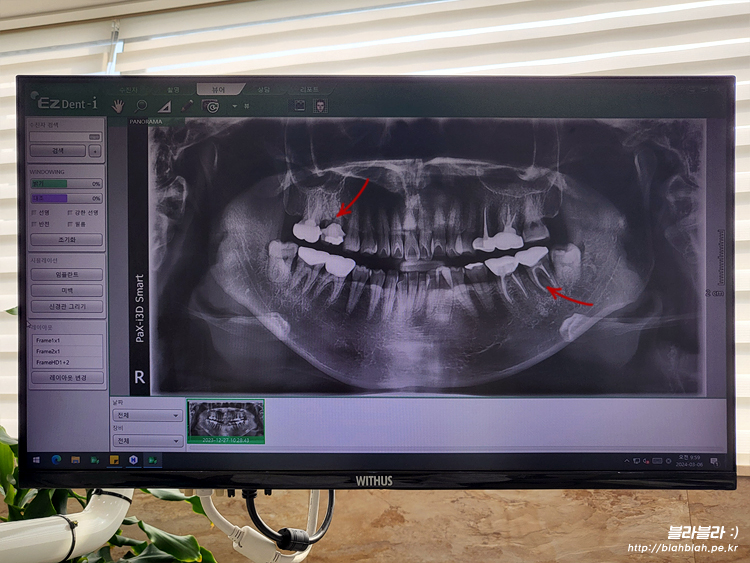

새로 방문한 치과에서 파노라마 사진 찍고

치주과 원장님과 만났습니다.

보시자마자 치아상태가 별로 좋지않고

제가 봐달라고 말씀드린 2군데 모두 임플란트행 ㅠ_ㅜ

이미 크라운 제거된 부분 먼저 임플란트 하기로하고

비용상담 받고 발치예약 했습니다.

윗니는 잇몸상태가 괜찮아서 발치하고 2달뒤 임플란트,

아랫니는 염증이 진행되어서 잇몸뼈가 녹았고

발치하면서 옆에 사랑니도 같이 발치하고

뼈이식 + 임플란트 ㅠ_ㅜ